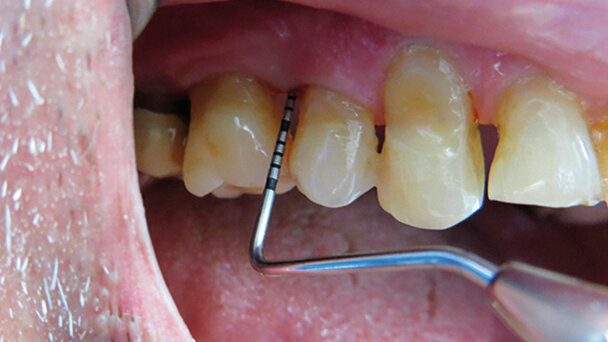

Un paziente, C.E., di 72 anni arriva alla nostra attenzione, accusando un fastidio generalizzato su tutto il cavo orale e una difficoltà masticatoria provocata dalla mobilità degli elementi superiori. Clinicamente riscontriamo, dopo aver effettuato un’accurata prima visita con ortopantomografia, una parodontopatia a carico di tutti gli elementi dentali, sia superiori che inferiori, con mobilità di secondo grado nell’arcata superiore, recessioni importanti generalizzate, ascesso parodontale a carico del 15 e tasche superiori a 5 mm in tutta la zona molare e premolare. È stata programmata una prima seduta d’igiene, in cui il paziente è stato ampiamente motivato all’importanza di una corretta e completa igiene orale, e un trattamento di levigatura radicolare per quadrante con un ciclo finale di clorexidina 0,20% per 15 giorni.

Al controllo, a distanza di un mese, il paziente riferisce un netto miglioramento in tutto il cavo orale con diminuzione della mobilità e scomparsa dell’infiammazione, situazione che è stata riscontrata anche clinicamente durante la visita. Unica zona in cui persisteva sia infiammazione sia mobilità era l’interdentale 15-16 con tasca di 8 mm a carico del 15 distale.

L’utilizzo del sistema HELBO consiste nell’inserire nella tasca parodontale, una sostanza di colore blu (cloruro di fenotiazina concentrato all’1%). Dopodiché si attiva il timer del T-Controller e si attende da uno a tre minuti, a seconda della profondità della tasca da trattare. In questo lasso di tempo il fotosensibilizzatore penetra nella membrana batterica. Successivamente si procede con un lavaggio della tasca, iniettando dell’acqua con una siringa e, dopo aver ben asciugato, s’inserisce la sonda del laser. Solo ora viene attivato il laser, irradiando per un minuto l’interno della tasca parodontale, soffermandosi 10 secondi su ognuno dei 6 punti classici del sondaggio parodontale. L’ampiezza del raggio della luce laser è di 360°, garantendo così la completa irradiazione dell’area da trattare.

Il colorante, attivato dalla luce laser, produce ossigeno singoletto che è aggressivo a tal punto da portare alla distruzione della parete batterica senza, però, arrecare alcun tipo di danno alle cellule circostanti. Inoltre, questo tipo di procedura con luce laser a bassa intensità, porta a una diminuzione del dolore, dell’infiammazione e a una biostimolazione tissutale, che si traduce in una rapida rigenerazione dei tessuti. Dopo aver terminato le tre sedute previste da protocollo, il paziente è stato rivisto a un mese per il controllo e a 4 mesi per la seduta d’igiene periodica.

Al richiamo quadrimestrale il signor C.E. non presentava più infiammazione a carico della gengiva degli elementi trattati, la mobilità era svanita e il sondaggio del 15 distale risultava ridotto da 8 mm a 4 mm. A oggi, dopo un anno e mezzo, il paziente presenta una situazione clinica stabile e ripete, in associazione a ogni seduta d’igiene, la terapia fotodinamica, come terapia adiuvante al trattamento.